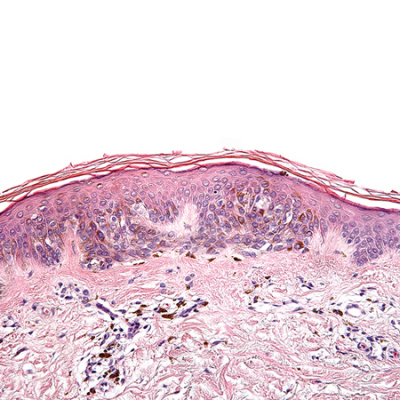

Risk of Melanoma in Moderately Dysplastic Nevi Excisionally Biopsied but With Positive Margins

Interview with Caroline C. Kim, MD, author of Risk of Subsequent Cutaneous Melanoma in Moderately Dysplastic Nevi Excisionally Biopsied but With Positive Histologic Margins